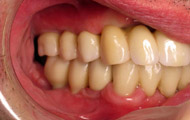

Exemple d’un implant unitaire pour remplacer une dent antérieure manquante.

Situation clinique initiale